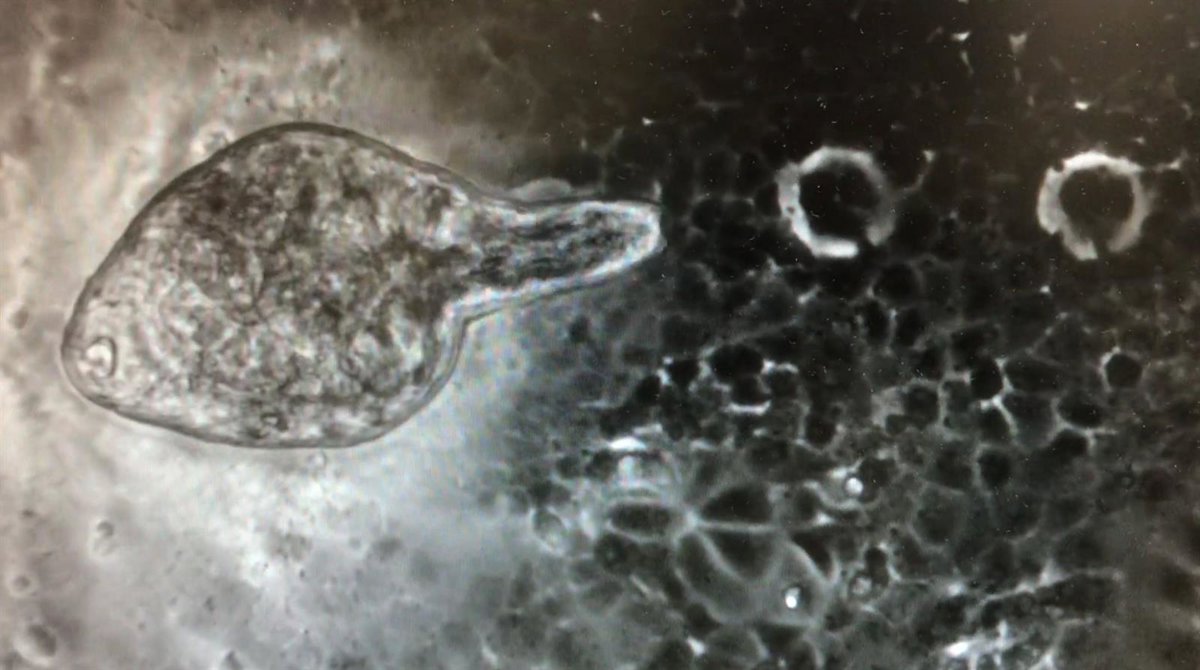

Ejemplar juvenil de Fasciola hepatica

Ejemplar juvenil de Fasciola hepatica - IRNASA-CSIC

En este estudio, en el que también ha participado el Instituto de Biología Integrativa de Sistemas (I2SysBio, centro mixto CSIC-Universidad de Valencia) se utiliza la especie Fasciola hepatica, helminto parásito con un ciclo de vida complejo que puede infectar a humanos, "produciendo fasciolosis, causada por la ingestión de metacercarias (su forma larvaria) en agua o plantas acuáticas", ha reseñado el Irnasa.